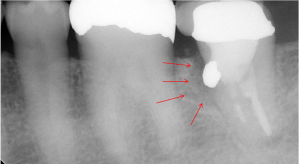

大阪の根管治療の専門の先生がこの方法を発明しまして、以下の写真の様にマイナスドライバーを2本使ってテコの原理を用い金属の土台を除去します。

80%以上この方法で金属の土台は除去することが可能です。